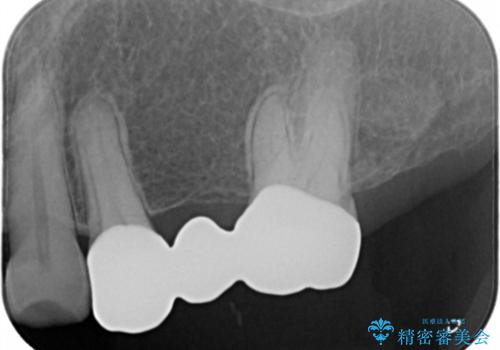

- 297,000円(フルジルコニアクラウン、仮歯それぞれ3本分)費用は治療当時の料金となります

露髄や痛みなどの症状も出ず、経過は良好です。